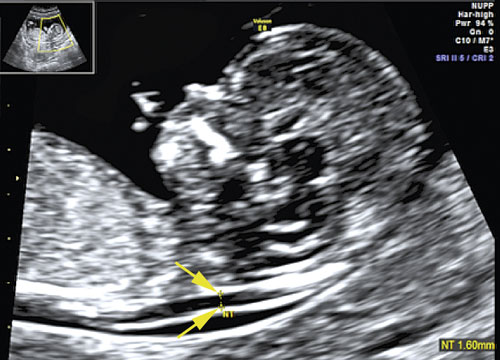

Tidigare hade man i årtionden använt moderns ålder som urvalsmetod för att erbjuda fosterdiagnostik och ge möjlighet till prenatal diagnos av trisomi 21 [2]. Successivt ökande genomsnittsålder hos gravida kvinnor och risk för missfall efter invasiv provtagning har gjort att en sådan policy inte kan anses vara medicinskt försvarbar. Metoden med ultraljud och mätning av fostrets nackuppklarning (NUPP) utvecklades vid Fetal Medicine Foundation vid King’s Col­lege i London under 1990-talet (Figur 1). Med en kombination av fostrets nackuppklarning och den gravida kvinnans ålder kunde ca 75 procent av foster med trisomi 21 detekteras om ca 5 procent av de undersökta hade positivt test och erbjöds invasivt prov [3].

Figur 1. Nackuppklarningsmätning i mittsagittalplanet vid ultraljudsundersökning av foster i vecka 12. Mätpunkter för maximal nackuppklarning markerade med kryss (vid pilar).